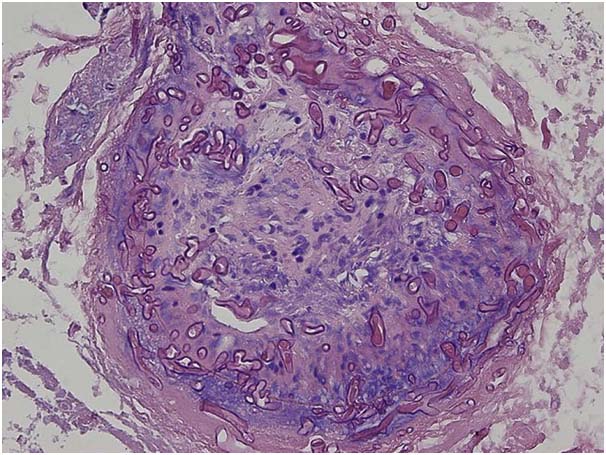

Mucormycosis toh ekta serious ase hoilebe etu toh samai-samai te ola fungal infection ase aro etu toh molds laga ekta group mucormycetes kowa para hoi. Etu fungi toh environment besi phak soil aro beya hoi thaka saman khan- compost piles, leaves nahoile rotten wood nahoile beya hoi thaka fruits aro vegetables nesana te thaki.

Fungal infection para sinuses, brain aro lungs te affect kori aro etu toh diabetic nahoile severely immunocompromised – cancer patients nahoile people with HIV/AIDS nesana khan nemite jevaan khatara ase.